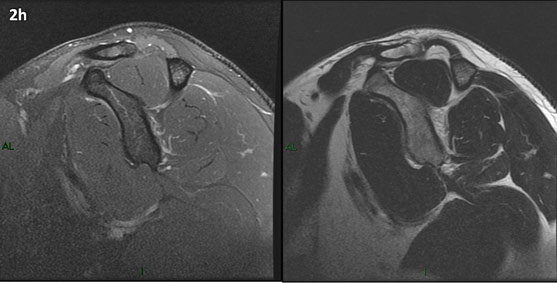

Figura 2 (a-j): Imagens consecutivas de RM no plano sagital nas ponderações T2 com supressão de gordura (DP SG) à esquerda e T2 à direita. Clique na seta para passar as imagens.

Figura 2 (a-j)': Imagens consecutivas de RM no plano sagital nas ponderaçõesT2 com supressão de gordura (DP SG) à esquerda e T2 à direita. Clique na seta para passar as imagens.

Figura 2a’ mostrando os tendões do subescapular (seta rosa), da cabeça longa do bíceps (seta verde), do supraespinhal (seta vermelha), do infraespinhal (seta laranja) e do redondo menor (seta amarela).

Figuras 2b a 2j’: Acompanhando o tendão do redondo menor (seta amarela fina) é possível notar lipossubstituição ao redor da junção miotendínea (setas amarelas grossas) e a atrofia principalmente da porção mais lateral (seta salmão). A porção mais medial (seta branca) tem volume preservado.

Repare que estas alterações também não são evidentes nas imagens com supressão de gordura no plano sagital.